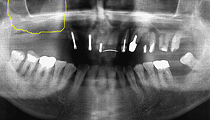

治療前のレントゲン写真。

黄色い線が上顎洞部分です。